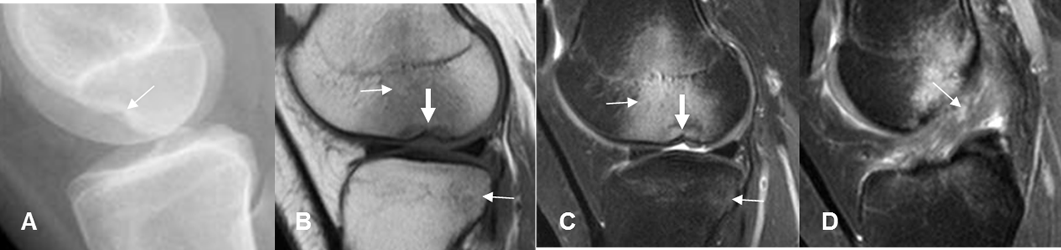

Fig 95 B. Signo de la muesca.

A: Rx lateral. Depresión en la parte inferior, del cóndilo femoral.

B: RM sagital en T1 y C: RM sagital en STIR. Contusión del cóndilo femoral y el platillo tibial lateral. (Flechas delgadas). Existe depresión significativa del cóndilo femoral. (Flecha gruesa).

D: RM sagital en STIR. Alteración en la señal y solución de continuidad, en la mayoría de fibras del LCA, por ruptura.